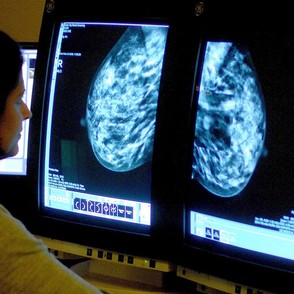

Δωρεάν μαστογραφίες από τον Δήμο Ηρακλείου Αττικής

Νέος κύκλος δωρεάν μαστογραφιών για τις Ηρακλειώτισσες από τον Δήμο – Ξεκίνησαν οι αιτήσεις

Την ευκαιρία να κάνουν δωρεάν μαστογραφία δίνει σε όσες Ηρακλειώτισσες θέλουν να εξεταστούν ο Δήμος Ηρακλείου Αττικής, μέσα από το νέο γύρο του προγράμματος που ανά τακτά χρονικά διαστήματα υλοποιεί σε συνεργασία με το Εθνικό Διαδημοτικό Δίκτυο Υγιών Πόλεων – Προαγωγής Υγείας.

Οι εξετάσεις αφορούν γυναίκες από 40 έως 69 ετών και θα πραγματοποιηθούν 21, 22, 28 και 29 Νοεμβρίου στο Κέντρο Μαστού (Τίρυνθος 2, Άνω Πατήσια) στις 9 το πρωί.

Οι αιτήσεις όμως συμμετοχής ήδη ξεκίνησαν και θα τηρηθεί σειρά προτεραιότητας. Οι ενδιαφερόμενες μπορούν να απευθύνονται στα Δημοτικά Ιατρεία της πόλης είτε από κοντά στον 2ο όροφο του δημαρχείου, είτε με τηλέφωνο στα 2132000196 και 187 κατά τις εργάσιμες ημέρες και ώρες.